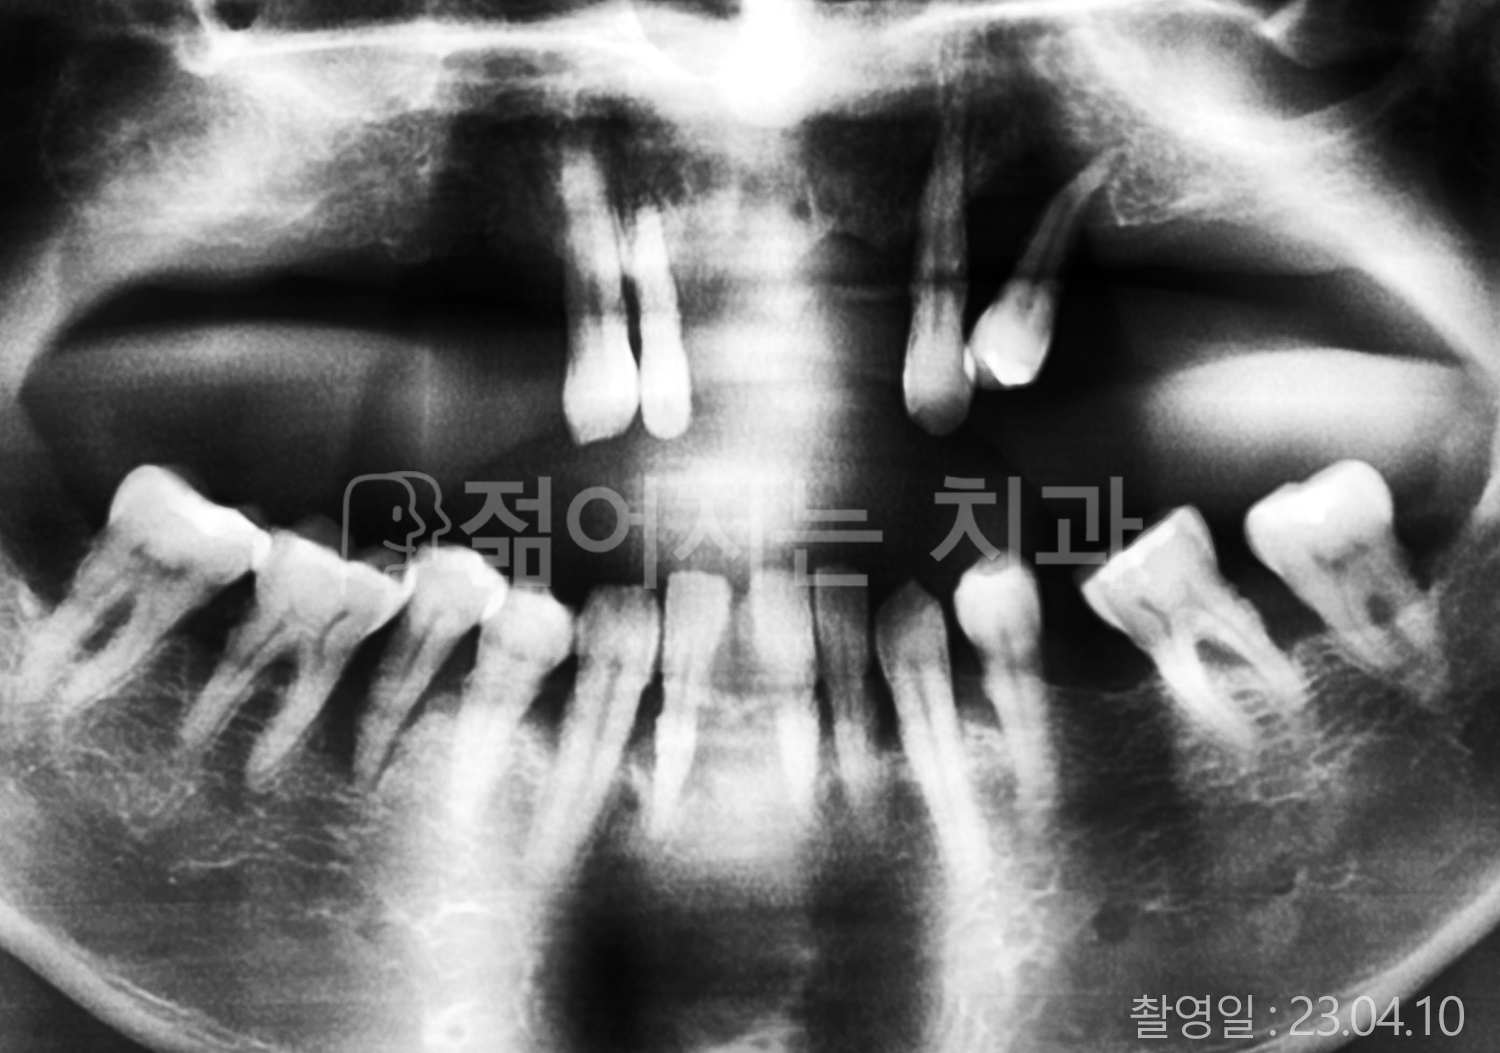

• 40대 전체치아 10개 이상 임플란트